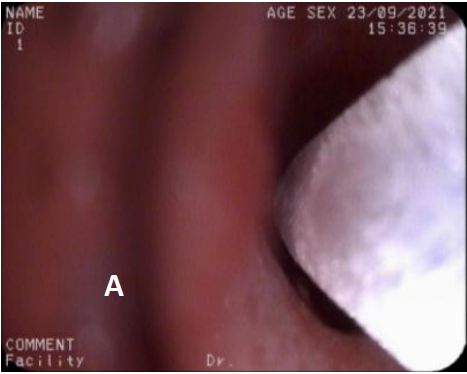

图5 第3次治疗(冷冻治疗+球囊扩张2021/9/23)

A. 冷冻治疗 B. 球囊扩张